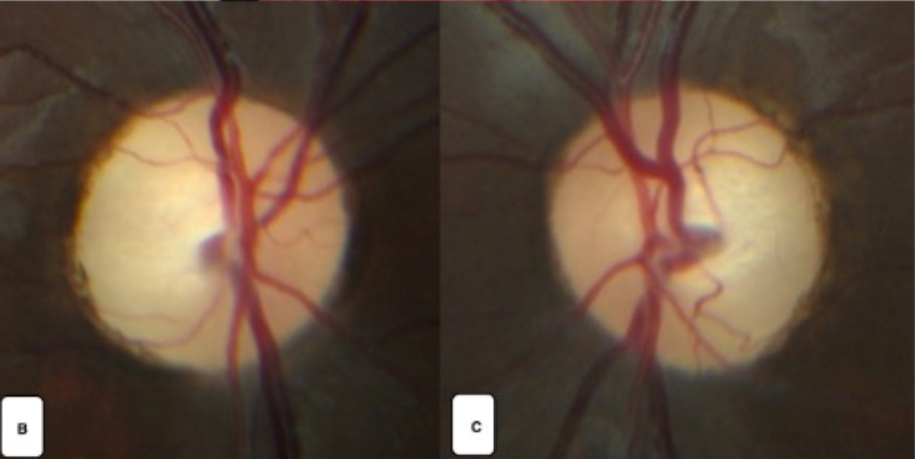

- Göz dibi muayenesi (fundus): Optik sinir başında solukluk, damar değişiklikleri ve sinir liflerinde incelme izlenebilir.